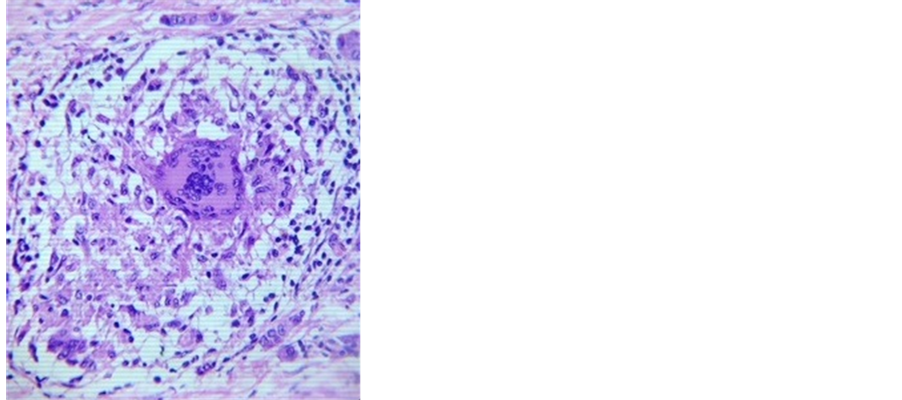

Histological evaluation of the specimen confirmed the diagnosis of invasive ductal carcinoma (Figure 3). However, in addition, granulomas comprising of outer rim of epitheloid cells typical of tuberculosis were seen in a few sections (Figure 4). Histopathological examination of axillary lymphnodes revealed positive evidence of metastasis in the lymph nodes. However there was no evidence of any granuloma. Post-operative recovery

Figure 4. Lymphoepitheloid granulomas am- idst malignant cells (Hematoxylin & Eosin staining, magnification ×40).